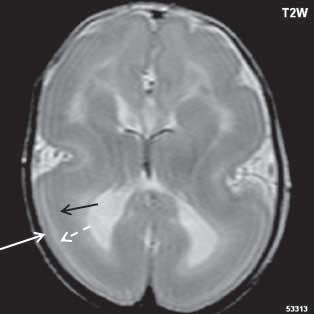

Zobrazení

CT je modalita málo senzitivní, prokáže ložiska denzity šedé hmoty mozkové, beze změn po aplikaci KL. MR je nejcitlivější zobrazovací metoda (optimální zobrazení šedé hmoty mozkové je technikou T1W + IR, naopak modalita FLAIR, velmi citlivá pro zobrazení změn bílé hmoty mozkové, nemá u heterotopie změny signálu nebo jen velmi diskrétní). Signálově ložiska heterotopie odpovídají šedé hmotě mozkové. Po aplikaci KL je beze

změn. Při ložiskové, subkortikální lokalizaci může být mozková kůra v jejich blízkosti zesílena, s projevy kortikální dysplazie.

Heterotopie šedé hmoty (subependymální forma) (šipka)

Obr. I.1.3c Heterotopie šedé hmoty (subependymální forma) (šipka)

Obr. I.1.3d Heterotopie šedé hmoty (subependymální forma); stejný pacient jako na obr I 1 3c

Obr. I.1.3e Heterotopie šedé hmoty (nodulární forma) (šipka)

Obr. I.1.3f Oboustranná subependymální heterotopie (šipky)